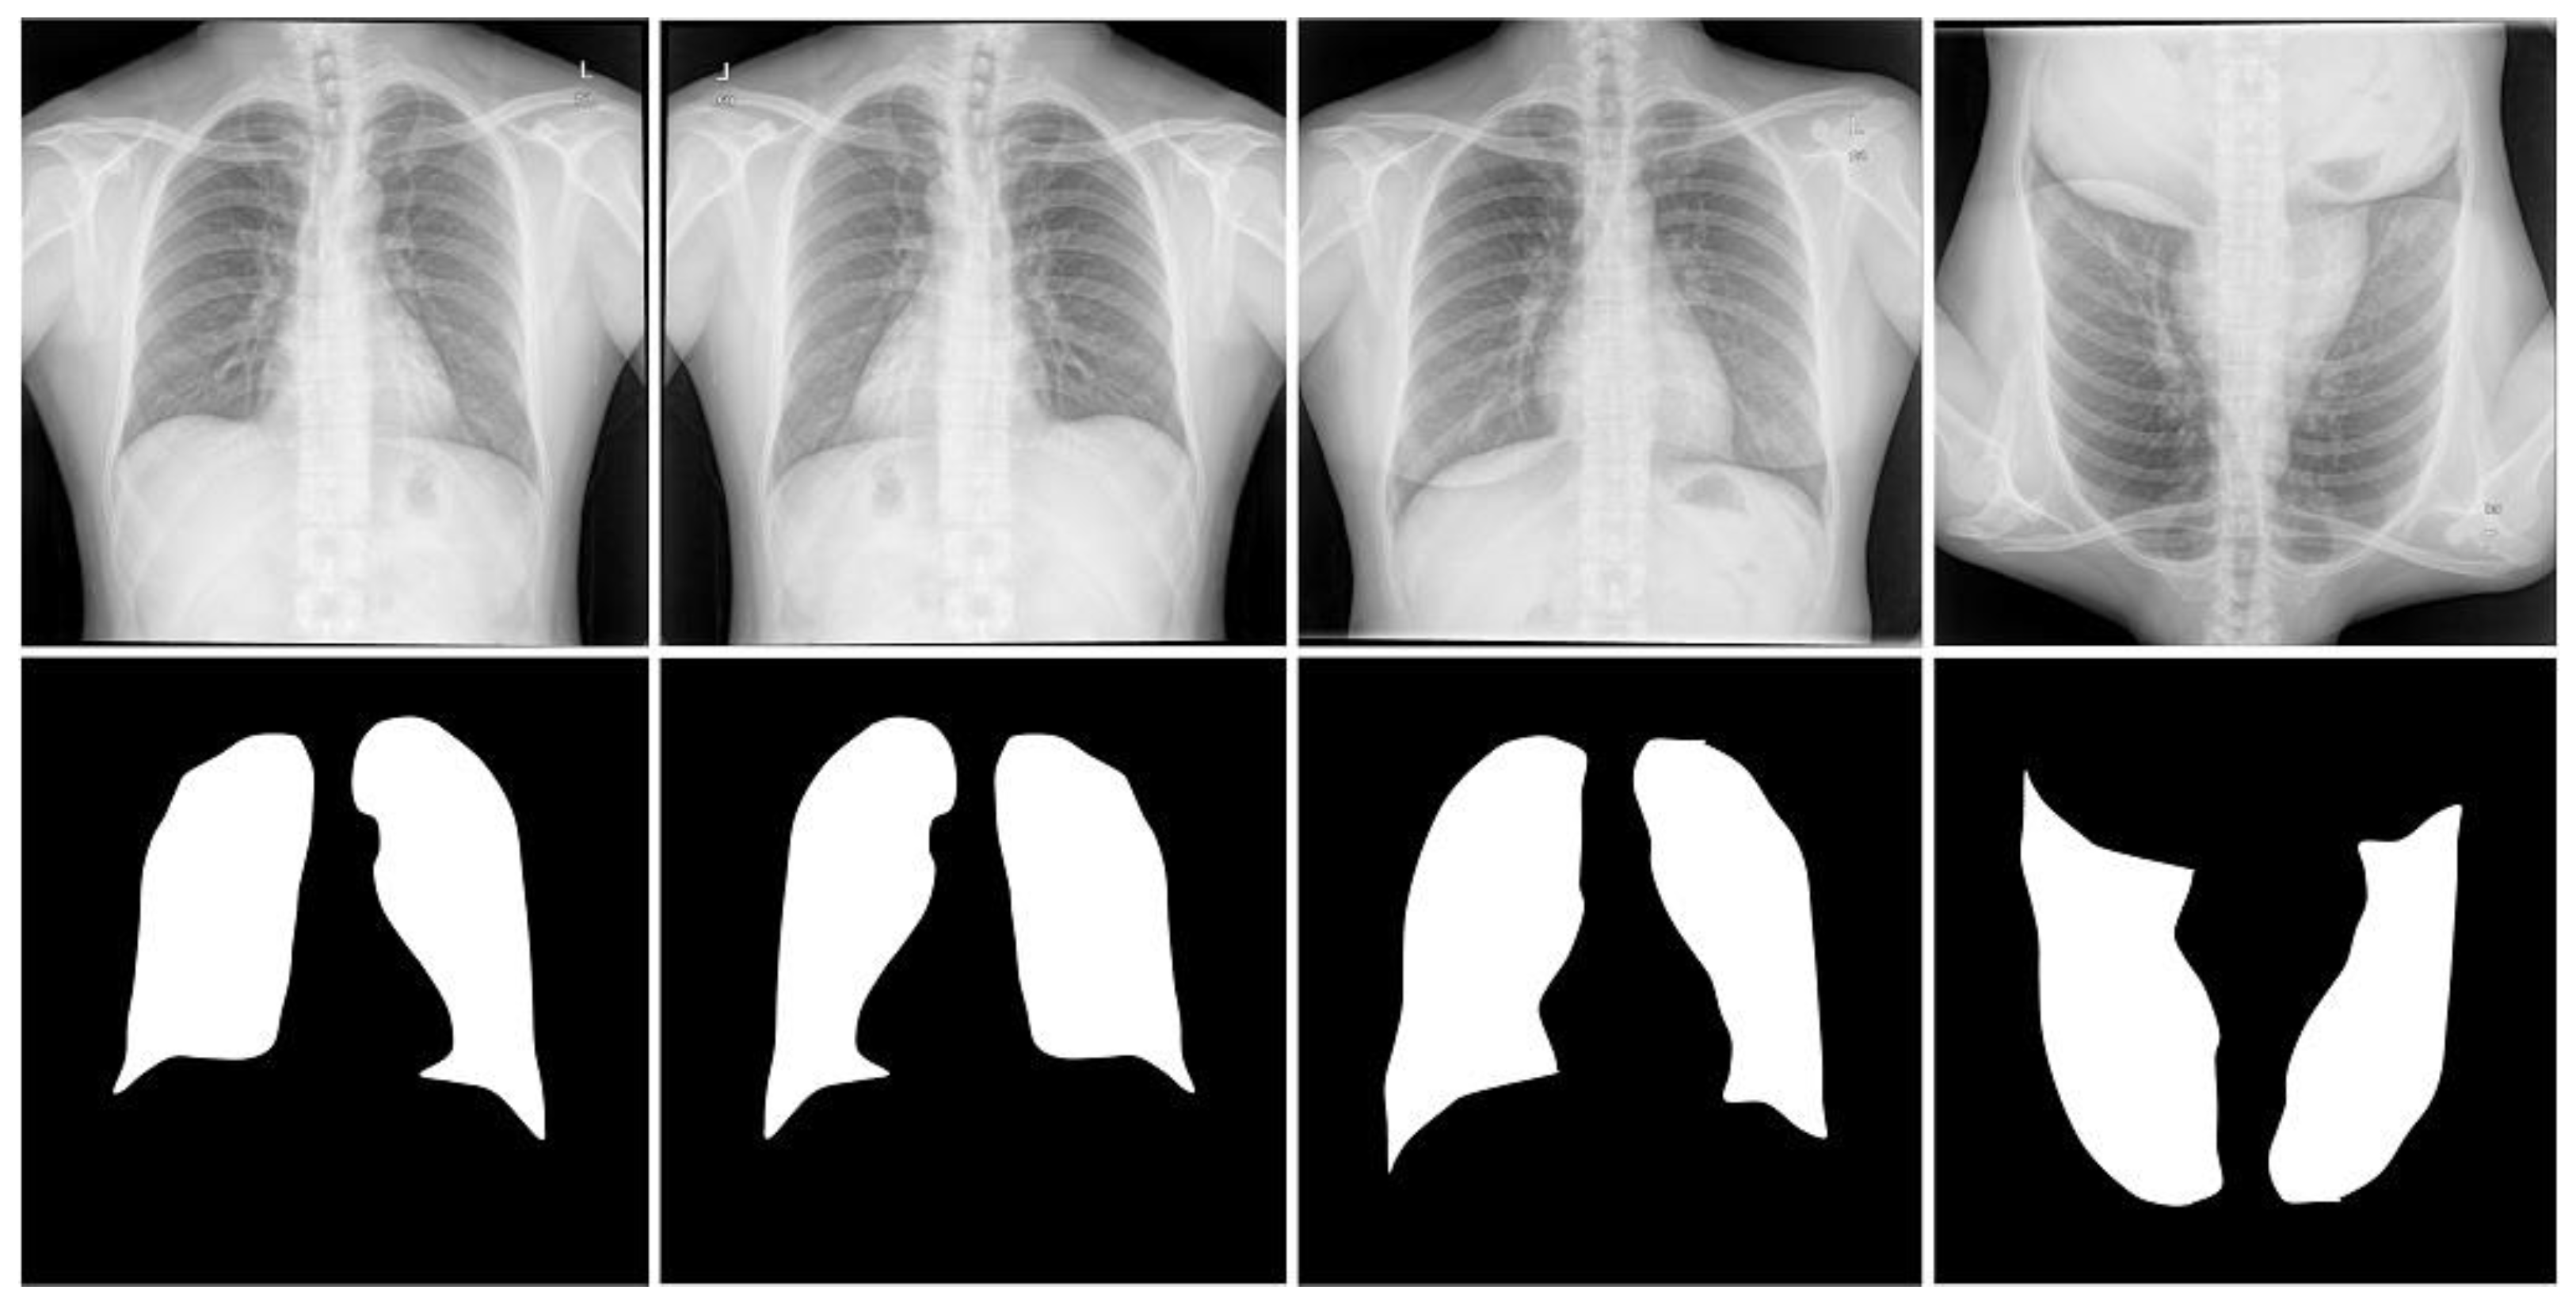

Figure 4.

Images and masks of the MC dataset.

Montgomery dataset [17]. Another dataset was created by the Montgomery County, Maryland, Department of Health and Human Services collection in the United States. It contains 138 radiograph images of the human chest region. Each CXR line slice is a single-channel grayscale image with a color bit depth of 8 and a resolution of or . In this dataset, 80 images are from healthy cases and 58 are from pulmonary nodules cases. We used one of the lung segmentation masks as a basic fact, labeled under the supervision of a professional radiologist and provided by Candemir et al. [29]. Similarly, we used two simple five-fold machine rotations and five-fold flip data enhancement strategies, and inserted the original image data into the expanded dataset together with the training; the dataset was expanded to eleven times the original, with 1518 images. We used 1210 images as training cases, 110 images as validation cases, and 198 images as test cases.